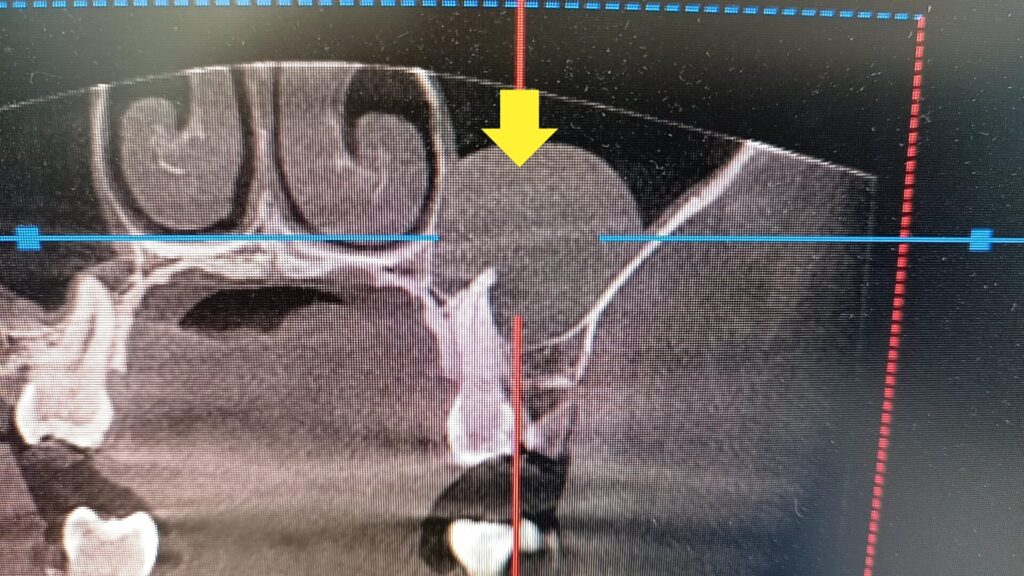

健康意識の高い患者さんだったので、CTを撮ってみることにしました。

すると。。

ななんと、上顎洞内に嚢胞とも思われる炎症の跡がありました。

結構大きいもので直径3センチぐらいはありそうです。

歯に原因がありそうなので精密検査してみることに